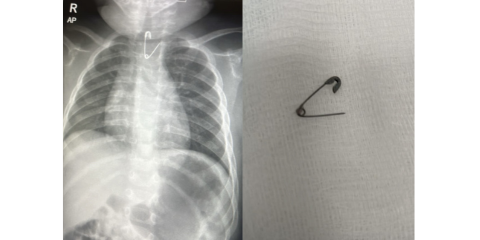

بعد ابتلاعه دبوسًا.. إنقاذ حياة طفل يبلغ من العمر 10 أشهر في مستشفى المواساة بالدمام